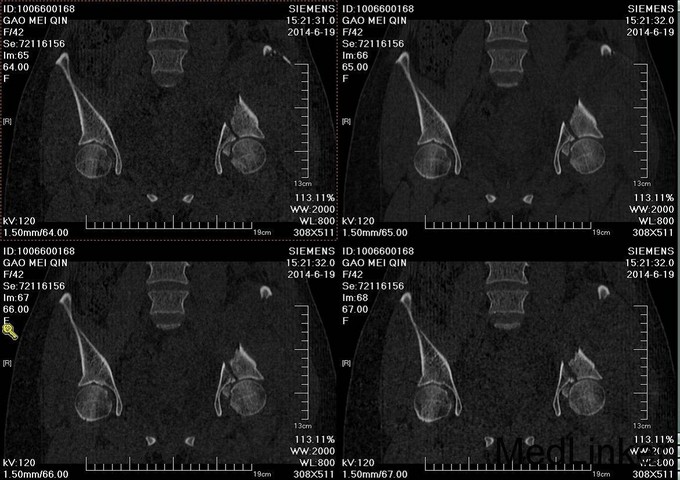

主诉:车祸外伤后左髋部疼痛伴活动受限4天 患者于2014年6月12日早6点左右被皮卡车撞伤,伤后患者出现一过性昏迷,被急诊送往当地医院,行DR及CT检查后,诊断为:左髋臼骨折,于当地医院骨科行骨牵引、抗炎补液等对症治疗后,现为求进一步治疗转入我科,患者病来无头晕头痛,无恶心呕吐,已排气排便.

患者左下肢股骨髁上骨牵引中,左髋部肿胀,臀部可见淤血瘀斑,骨盆分离挤压试验(+),左大腿肿胀,左下肢无明显短缩,纵向叩击痛(+),左下肢小腿外侧及足背麻木感,足背伸肌力正常,双足趾可活动,双侧足背动脉可触及搏动